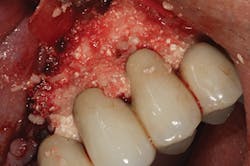

Peri-implantitis has been defined as an inflammatory process that affects the tissues around an osseointegrated implant in function and, like periodontitis, results in loss of supporting bone6 (Figs. 3 and 3a). The prevalence of peri-implantitis has been shown in some studies to range from 11% to as high as 47% of implant sites analyzed.(16) Most literature reviews agree that once bone loss has occurred around an implant, nonsurgical therapy is not as effective as surgical treatment.(17) Surgical intervention by the dentist or specialist includes raising a full thickness flap around the affected dental implant in order to completely expose the dental implant surface (Fig. 4). Mechanical debridement with hand and high-speed instrumentation as well as irrigation with various medicaments is advocated in order to detoxify the implant surface and alleviate bacterial contamination. After decontamination, the flap can be apically or coronally positioned. In addition, various regenerative technologies, including bone and soft-tissue grafts, growth factors, and barrier membranes have been used to rebuild lost tissue support around the dental implant (Figs. 5 and 5a). Different methods of guided bone regeneration around implants affected with peri-implantitis were demonstrated, and the results have been shown to be stable for a follow-up period of up to seven years.(18) That being said, no gold standard of peri-implant disease has been documented and "available evidence does not allow specific recommendations for the therapy of peri-implantitis."(19)